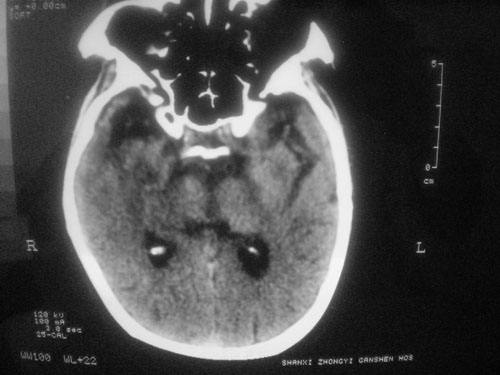

脑供血不足的症状CT图